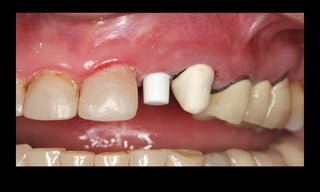

Resultados estéticos periimplantares otimizados

(Abboud, M. IJOMI, 2005).

10-10-2005

Novembro de 2005

24-01-2006